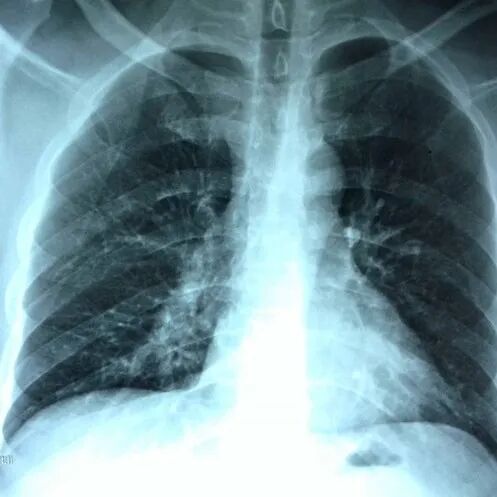

肺癌是发病率和死亡率增长最快 对人群健康和生命威胁最大的恶性肿瘤之一 换言之 发现得越早 治疗效果越好 我们与新华日报交汇点直播平台 江苏省科学传播中心合作 并邀请到了江苏省人民医院(南京医科大学第一附属医院)胸外科主任医师朱全 和我们聊一聊从肺结节到肺癌,如何实现精准诊疗? 专家简介 朱全,主任医师,江苏省人民医院胸外科副主任。中华医学会胸心血管外科学分会胸腔镜学组委员,中华医学会江苏省胸外科分会委员。 01 肺结节的性质 肺结节:< 3厘米 主要是指肺实质内单发或多发直径不超过 3 厘米 的圆形或类圆形结节影。不伴肺不张、肺钙化、肺门淋巴结肿大或胸膜渗出。 结节: <8毫米时称作亚厘米结节 <4毫米称作微结节 肿块: ≥ 3厘米 02 肺结节的分类 (1)实性结节 (2)半实性结节 (纯磨玻璃结节、混合磨玻璃结节) 实性结节 混合磨玻璃结节 结节分类 磨玻璃样结节 03 肺结节≠肺癌 •实性结节恶性率仅7% •部分实性结节恶性率为63% •纯磨玻璃结节恶性率为18% •>20 毫米的结节恶性率有80% 肺磨玻璃肺结节的演变 01胸部X光平片 对肺癌的漏诊率30% 不能发现肺小结节 02 薄层CT 5mm层厚已成为历史---导致误诊! 薄层CT比常规CT提供了7-10倍信息 (普通CT 60张对比 薄层CT 360-600张) 03 正确使用PET/CT • 能够评估结节的代谢活性。 • 对大于1厘米的实性结节有意义 • 对纯磨玻璃和混合性磨玻璃结节无效 • 不易区分炎症和结核 强调!!! 磨玻璃结节要经过随访 2-3个月的随访很重要 炎症的比例10% 随着时间会消失 肺结节CT影像AI辅助检测 外科手术的微创化 切口的微创化 全胸腔镜→3孔→2孔→单孔 肺切除范围的变化 非解剖性肺切除:楔形 解剖性肺切除:全肺切除、肺叶切除、肺段切除术、肺亚段切除术、肺次亚段切除术 肺段切除 早期肺癌的微创治疗外科手术的精准化 早期肺癌外科治疗中的规则: 保证肿瘤学效果是首要任务保留更多有功能的肺组织 三维CT支气管血管成像(3D-CTBA)肺结节与早期肺癌